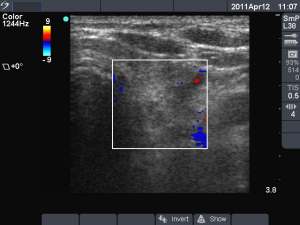

First session (first row of images):

Clinical presentation: the patient told us that her persistent cough lasting for several month have stopped after removal of cystic fluid for five or six weeks. Thereafter this complaint recurred.

Palpation: no abnormality.

Ultrasonography: the cysts has recurred.

We offered ethanol sclerotherapy. We aspirated 4 mL watery fluid and administered 1.5 mL ethanol.